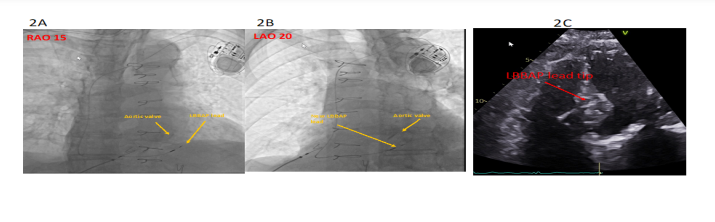

The patient was urgently taken to the electrophysiology laboratory for pacemaker implantation. Because of his history of cardiomyopathy and anticipated frequent ventricular pacing, he was considered to be at increased risk of recurrent cardiomyopathy induced by right ventricular (RV) apical pacing. Additionally, because previous studies suggest that RV apical pacing or LV epicardial pacing may promote arrhythmogenicity, we elected to proceed with a trial of LBBA pacing. Through an axillary vein access, a Medtronic C315 delivery sheath was advanced to the RV septum in the vicinity of the LBB area (1.5 to 2 cm distal to the tricuspid annulus towards the ventricular apex). A Medtronic 3830 lead was advanced over the delivery sheath and penetrated the ventricular septum to engage the left bundle. At the final location, pacing demonstrated abrupt conversion of the paced QRS from a LBBB morphology to a much narrower RBBB morphology. An LV activation time (measured from pacing stimulus to R wave peak or S-RWPT) in V6 of 90 ms and a paced QRS duration of 120 ms suggested likely recruitment of the left bundle-Purkinje system. Pacing at high and low output demonstrated fixed S-RWPT with excellent sensing and pacing thresholds. The procedure was completed successfully without complications. The procedure time from lidocaine injection to pocket closure was 16 minutes with a fluoroscopy time of 1.6 minutes. A post-operative chest x-ray showed satisfactory lead position and an echocardiogram showing LBBA pacing lead seated appropriately in the deep septum (Figure 2).

Figure 2: Demonstrating the left bundle branch area pacing lead position shown in RAO and LAO views on chest fluoroscopy (2A and 2B) and post-operative ECHO (2C).